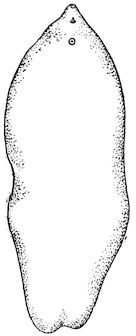

114. The fourth phase, or period of osteomalacia, i.e. softening of the bones, is also the last. It is rarely seen in large animals like horses and oxen, because accidents so often accompany the preceding stages and necessitate slaughter; but it is common in goats and pigs.

In this phase the bones become elastic, soft and depressible, yielding to the pressure of the operator’s fingers.

In the goat, the disease shows some slight peculiarities. Thus, in the second phase, during which goats and sheep suffer so markedly from lameness and pain in the bones, goats often walk on the knees. The disease, however, is uncommon in these animals. The phase of osteoclastia is also less marked and fractures are rare, because the animals weigh less and also because they are less exposed to falls and violent shocks. The bones, nevertheless, are extremely fragile and fractures may be produced at will.

Regarding the development of the disease in pigs, we may repeat what has just been said respecting the goat. Walking on the knees is often one of the first signs, fractures are somewhat rare, and the period of softening and deformity is always very noticeable.